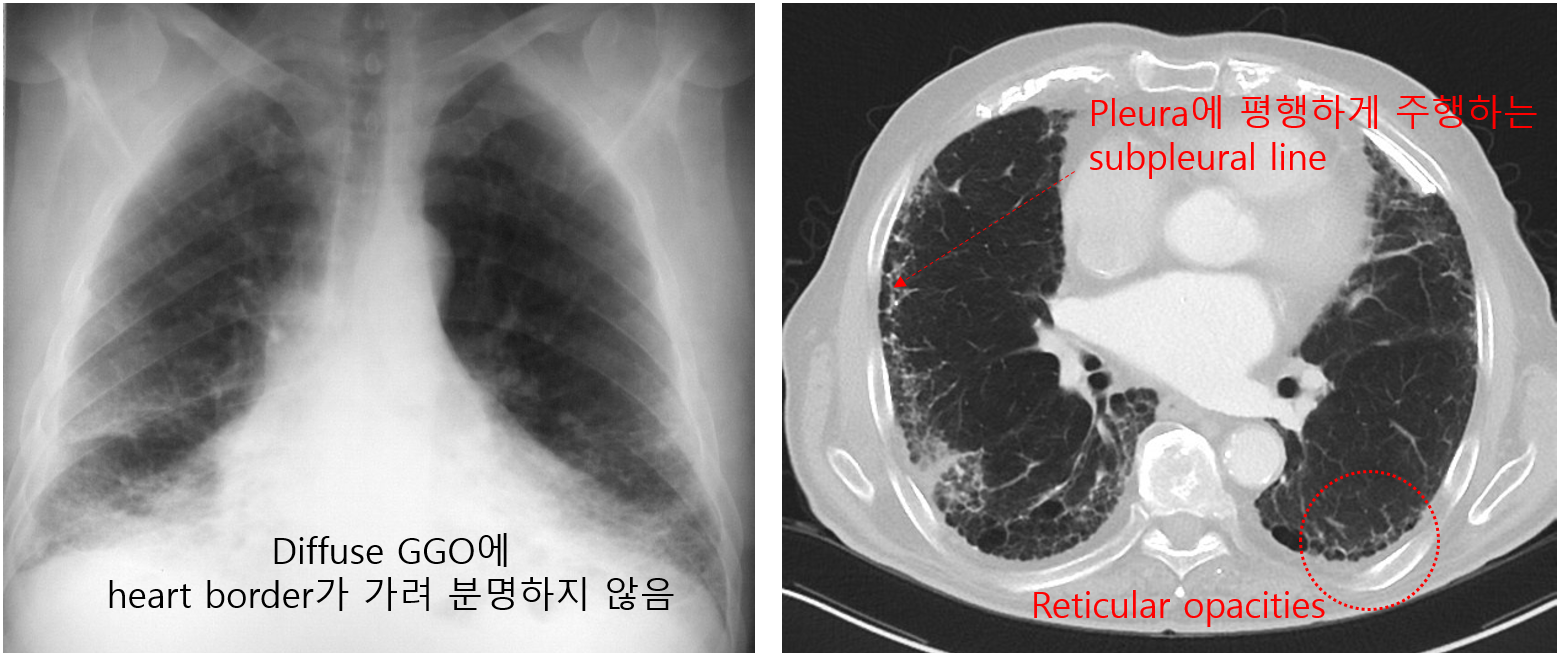

(1) CXR/CT

① 석면폐증: 폐하부 diffuse GGO, sagging heart, reticular opacities, subpleural line 등

(2) PFT: 제한성 양상 (폐용적, DLCO 감소)